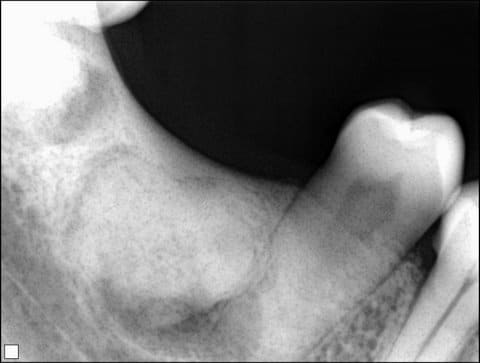

Une image radio du secteur 4. Femme de 40 ans. Aucun symptome particulier. Cela vous fait penser a quoi? On envoie chez le stomato ou pas pour explorer?

Dysplasie cémento-osseuse de type focale si le secteur 40 est seul touché.

La lésion devait exister probablement avant les avulsions mais a pu évolué.

si il existe d'anciens clichés, c'est intéressant.

pas de traitement à prévoir jusqu'à nouvel ordre.